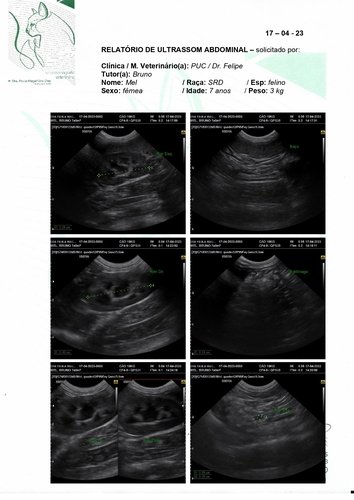

Olá, meu nome é Mel tenho 7 aninhos e peso 3kg (sim, sou bem pequinininha pra minha idade e comparado ao meu irmão de ninhada). Eu e meu maninho Cheetos fomos adotados pelo meu papai Bruno quando nossa antiga tutora faleceu. Nós ja tinhamos 2 aninhos na época, e nunca degrudamos um do outro nesses anos todos. Desde quando meu papai nos acolheu tínhamos que ficar separado da nossa irmã mais velha porque eu sempre fiz meu xixizinho em todo lugar que eu vejo, não faço na caixa de areia e nem mesmo cubro quando decido fazer lá. Mas nunca faltou carinho e amor independente de tudo. Recentemente papai e mamãe decidiram me levar no veterinario para ver o que seria esse problema de xixi em todo lugar, o doutor pediu ultrassom e infelizmente descobrimos a princípio um tumor bem grande perto da bexiga (o qual poderia ter deslocado minha bexiguinha e talvez possa explicar algumas coisas). O doutor disse que teríamos que fazer uma tomografia em outro estado pois onde moramos não tem, e pelas contas dos meus papais ia ficar mais de R$2000,00 fora a cirurgia ><. Mas o doutor disse que podemos ir direto pra cirurgia pra tentar solucionar e não alastrar mais o tumor. Quando chegamos para a cirurgia nao pude fazer por ter fugido do jejum porem me pediram pra refazer os exames e nisso apareceu que o que era um tumor parecia mais uma castração mal feita que tinha deixado partes do ovario e tava causando infecções. Meus papais vieram pedir ajuda pois a cirurgia vai ficar cara fora os medicamentos.

Vamos anexar aqui todas fotos, exame e valor da cirurgia! Qualquer ajuda é bem vinda e contamos com vocês pra logo logo eu ficar bem de novo e poder ficar grudada brincando com meus irmãozinhos!! <3